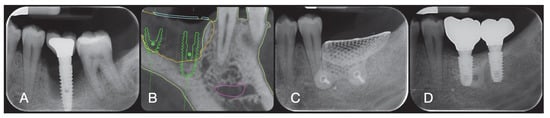

2.5. GBR Procedure

2.6. Outcome Measures